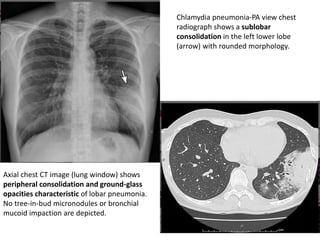

Chlamydia pneumonia-PA view chest

radiograph shows a sublobar

consolidation in the left lower lobe

(arrow) with rounded morphology.

Axial chest CT image (lung window) shows

peripheral consolidation and ground-glass

opacities characteristic of lobar pneumonia.

No tree-in-bud micronodules or bronchial

mucoid impaction are depicted.

Chlamydia pneumonia-PA viewchest radiograph shows a sublobar consolidation in the left lower lobe (arrow) with rounded morphology. Axial chest CT image (lung window) shows peripheral consolidation and ground-glass opacities characteristic of lobar pneumonia. No tree-in-bud micronodules or bronchial mucoid impaction are depicted.